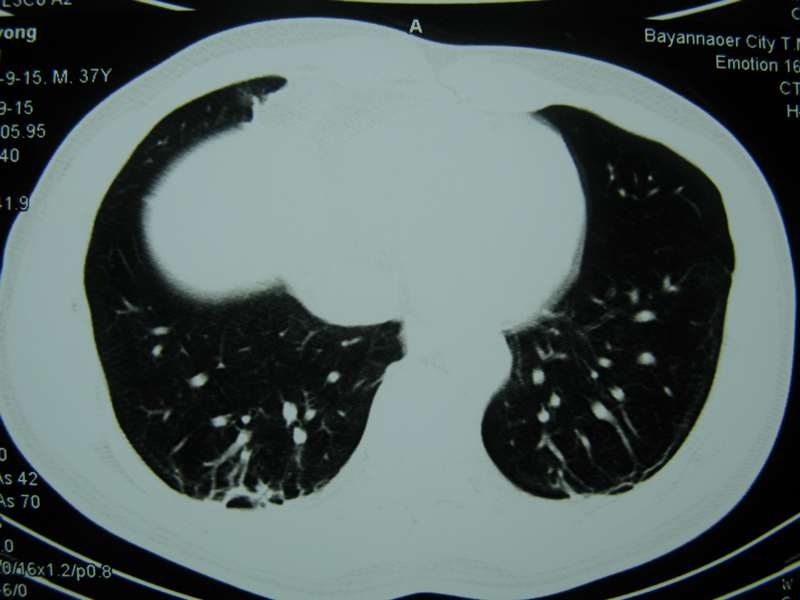

男,37岁,主述胸疼厉害,无咳嗽,无发热,血象也不高,病灶内ct值脂肪密度,右侧胸腔内少量积液,同道们考虑什么?谢谢!

脂肪垫,右下肺感染,少许积液是症状所在

纵膈脂肪堆积,右肺慢性炎症。

两肺下叶基底段纤维灶,右肺下叶基底背侧相应胸膜肥厚,右肺中叶内侧段部分不张。前中下纵隔团块状脂肪影,随访除外胸腺脂肪瘤。

纵膈脂肪堆积,右肺慢性炎症

脂肪垫;右肺慢性炎症。

不除外膈疝。